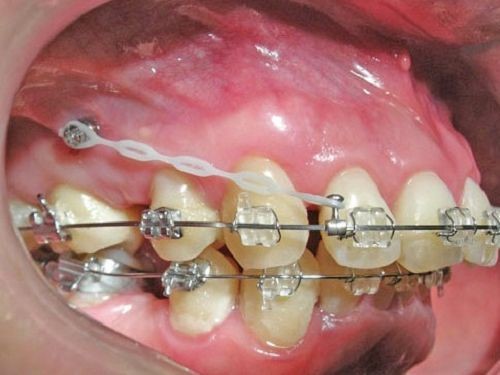

矯正用インプラントは、直径1~2mm程度の小さなチタン製ネジを顎の骨に一時的に埋め込み、そのネジを固定源として歯を効率よく動かすという治療法です。

ワイヤー矯正、マウスピース矯正と組み合わせることで、歯を後方に引く力を強め、出っ歯をより正確かつ短期間で改善できるのが特徴です。